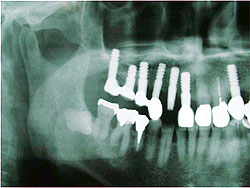

AQBは、結晶体の密度が高く純度も高いことが特長であり、三井記念病院におけるAQBインプラント症例では、最長18年を経過した臨床例においても、歯槽骨の状態は変わらず、逆に密になっていることが分かっている。そこで、上顎臼歯部の骨吸収症例において、サイナスリフトと同時にAQBインプラント1ピースを植立し、自家骨移植や人工骨移植を行わず、治療を行った症例を報告した。6例に施行し、全例、予後良好で、すべて植立後4ヵ月以内で咬合を開始した。GBR症例においてもAQBインプラント2ピースを埋入し、自家骨移植や人工骨移植は行わず、チタン入り非吸収性膜を用いたスペースメーキングを行った。その結果、4ヵ月後には歯槽骨の再生を確認した。

| AQBを用いて歯槽骨再生を図った症例 | |

サイナスリフト症例 ▼ ![]() 術前 ![]() 術直後 ![]() 術後4ヵ月 |

GBR症例 ▼ ![]() 術前 ![]() 術直後 ![]() 膜除去直後 |